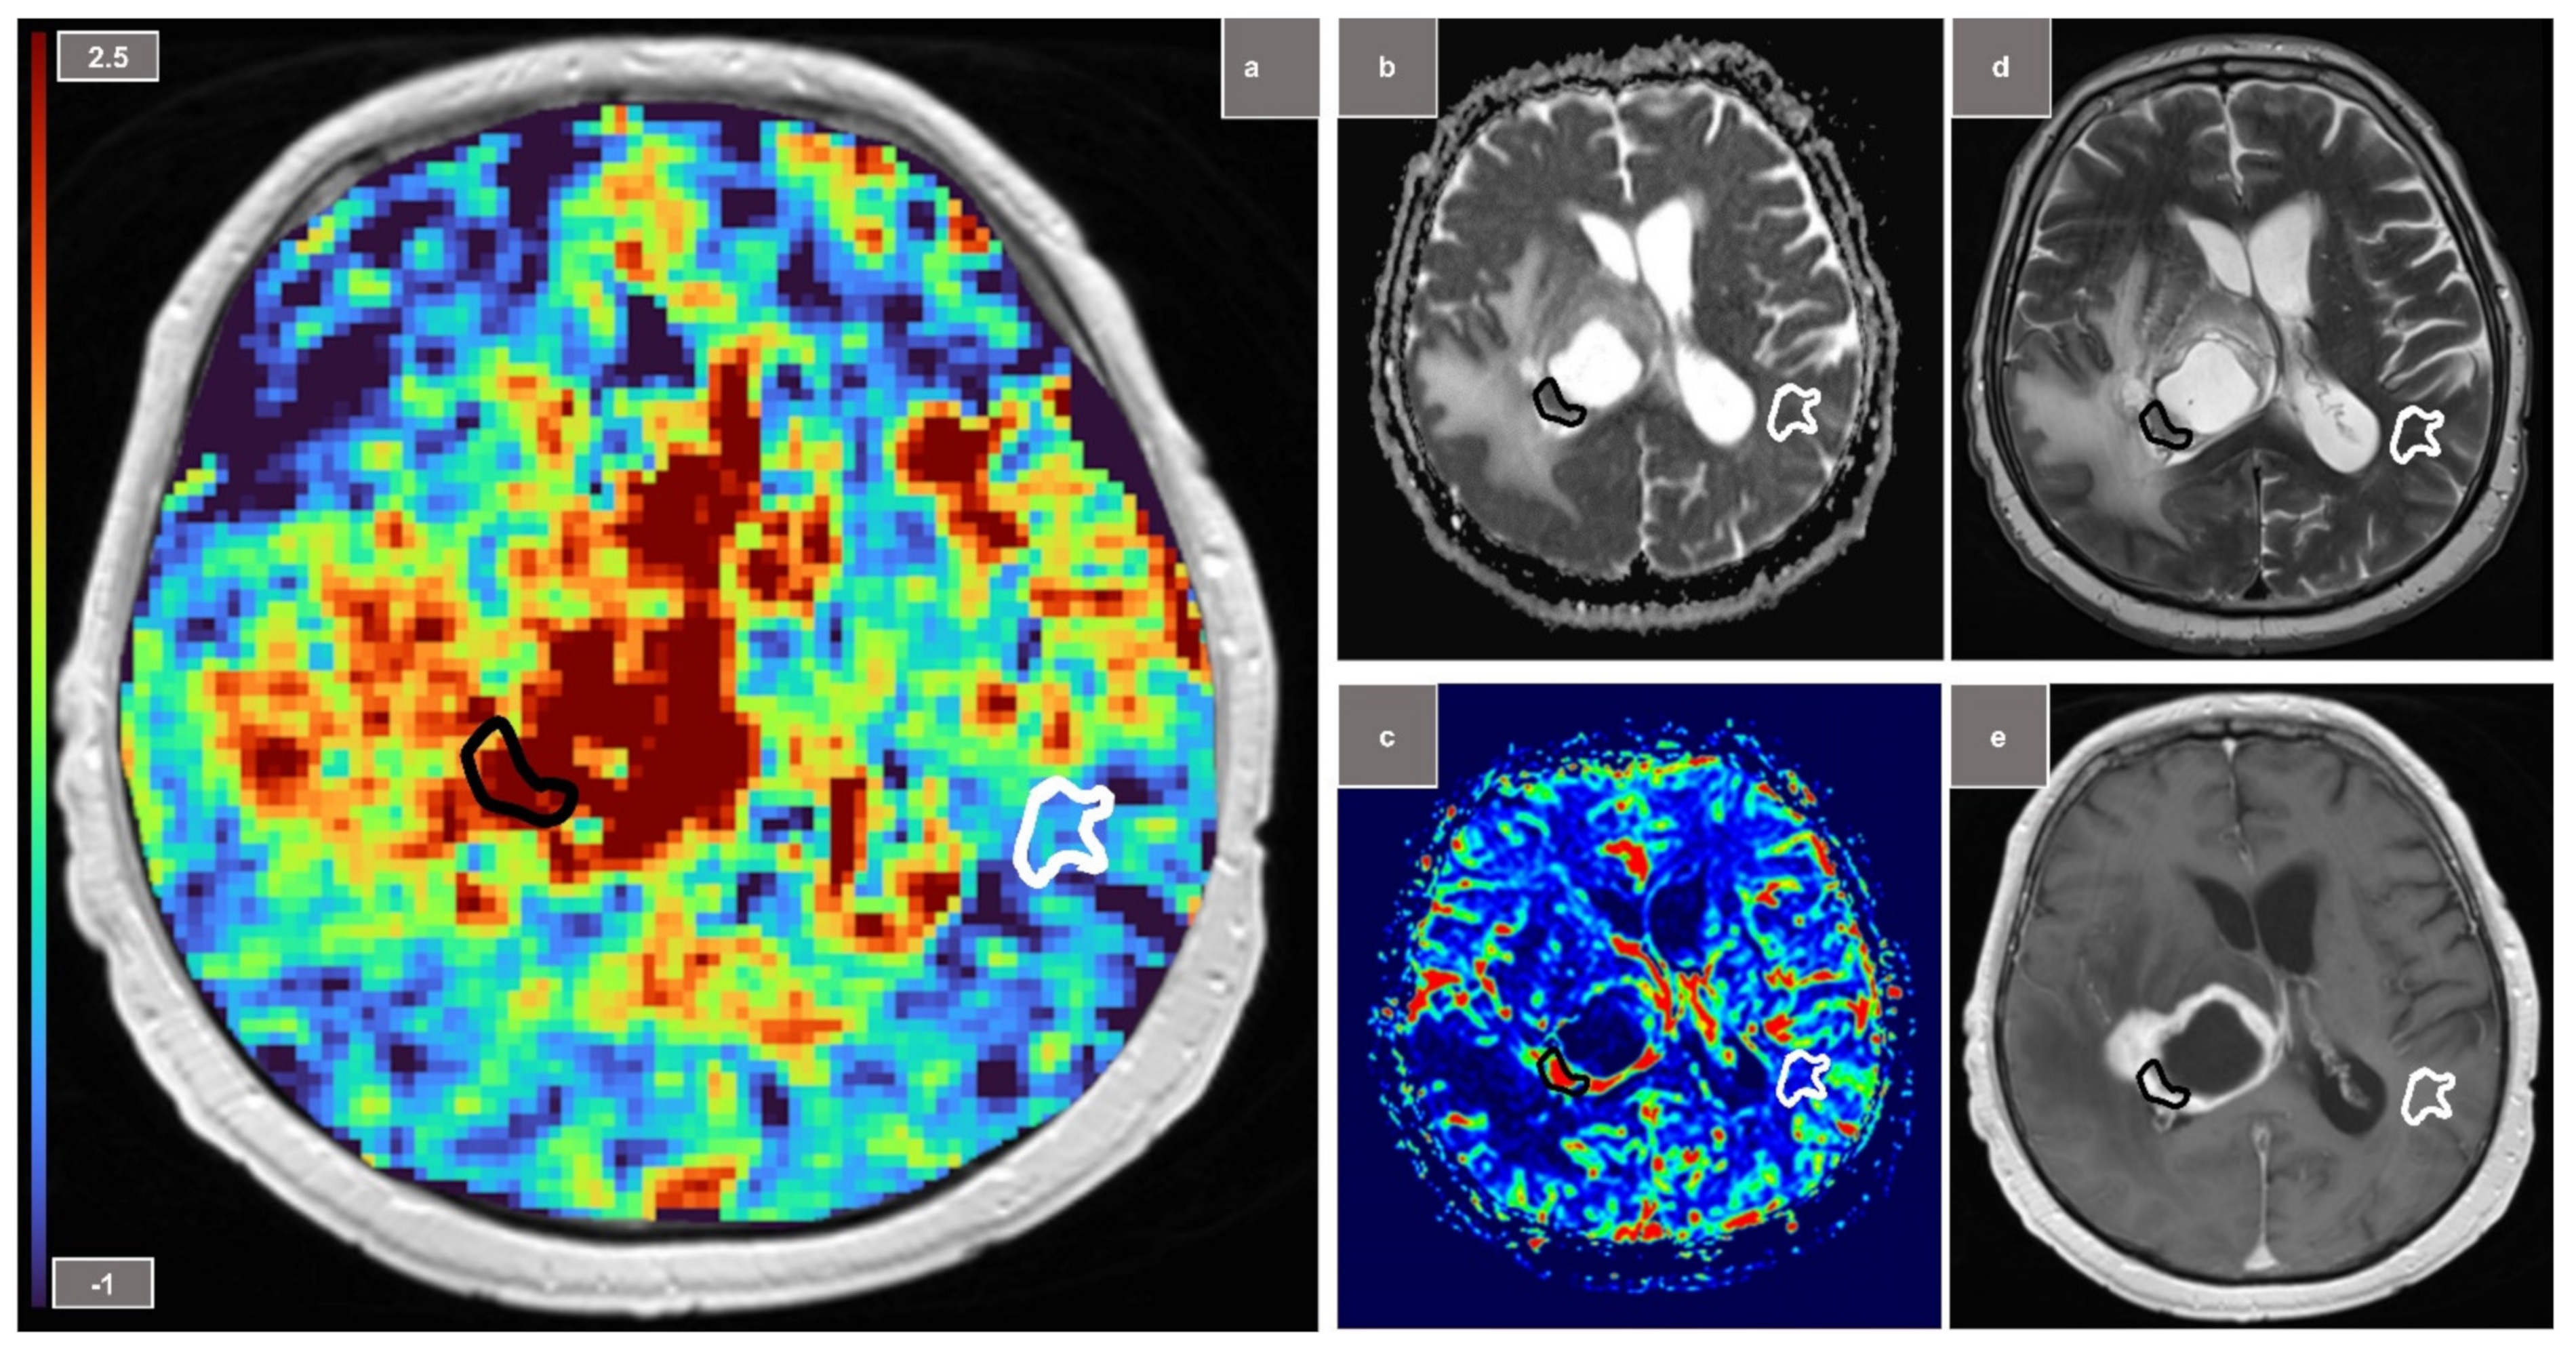

Following subgroup analyses of each tumor entity vs. NAWM, statistically significant effects were found for the subgroups of glioblastomas (sensitivity/specificity: 100%/80%; AUC = 0.96; p < 0.01) (Figure 2) and meningiomas (100%/100%; AUC = 1.0; p < 0.01) but not for lymphomas (100%/50%; AUC = 0.75; p = 0.18) and metastases (73%/82%; AUC = 0.67; p = 0.2). In comparison, ADC metrics showed significant distinction in the subgroups of glioblastomas (100%/80%; AUC = 0.84; p = 0.02), metastases (82%/73%; AUC = 0.84; p = 0.04) and lymphomas (100%/100%; AUC = 1.0; p < 0.01). rCBV analysis showed a similar high performance to APTw CEST metrics in order to differentiate between glioblastomas and NAWM (100%/100%; AUC = 1.0; p < 0.01).

Figure 2.

Glioblastoma with tumor ROI (region of interest) marked in black and NAWM (normal-appearing white matter) ROI outlined in white. (a) Amide proton transfer-weighted chemical exchange saturation transfer (APTw CEST) map (b) ADC (apparent diffusion coefficient) map (c) relative cerebral blood volume (rCBV) map (d) T2-weighted TSE (e) gadolinium contrast-enhanced T1-weighted image.